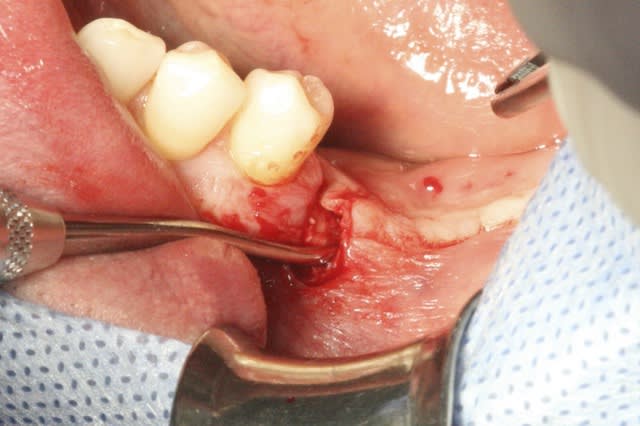

image 2: prélèvement Ramique

image 3 et 4: découpe d'une fine lame allant servir de toit

image 6: insertion du "toit"

image 7: fixation ( vis Stoma)

Désolé pour la qualité, c'est tout ce que j'ai..